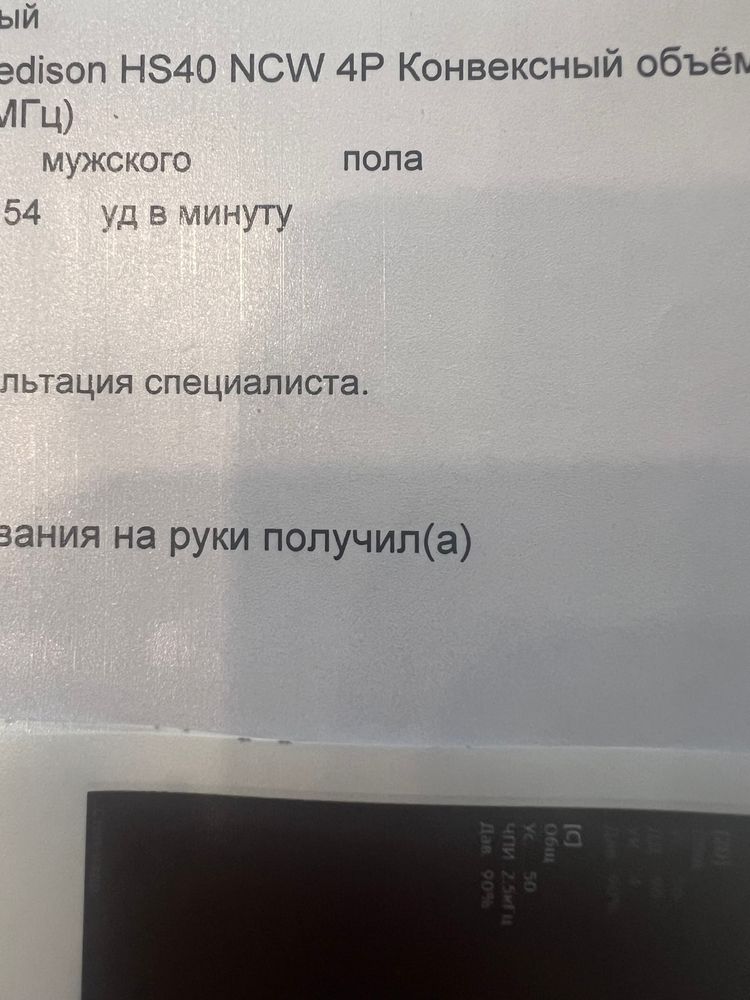

Здравствуйте,вчера были на узи по определению пола, утверждено предположили мальчика, срок по скринингу 15 нед 5 дн , что скажете?